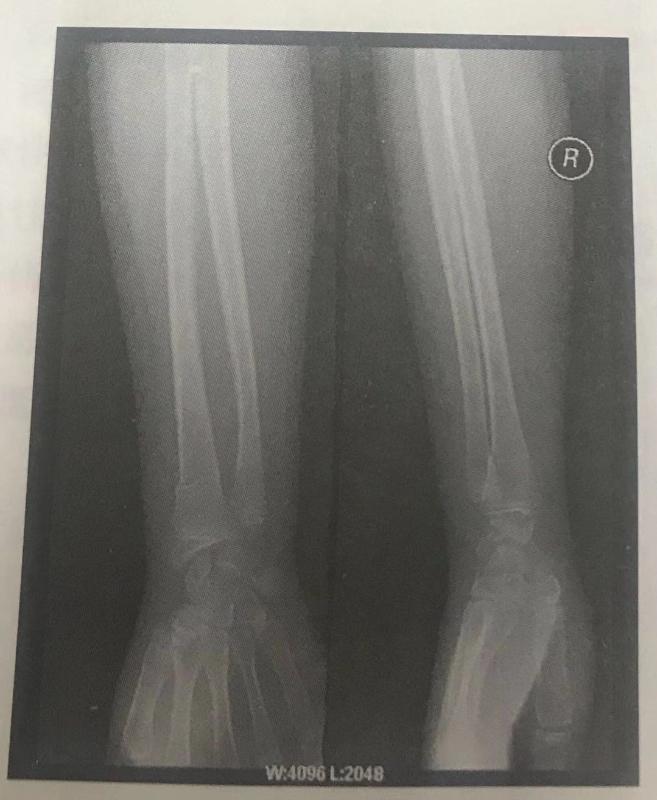

根据下面X线片判断临床意义。(5分)

右挠骨远端青枝骨折